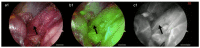

We present the first case of fluorescence-guided surgery (FGS) using indocyanine green (ICG) in a pediatric redo-Nissen fundoplication. The patient is a 17-year-old male with recurrent gastroesophageal symptoms who underwent primary antireflux surgery at 10 months of age. During the redo fundoplication, ICG was intravenously administered to help the visualization during the adhesiolysis between liver, stomach and right crus of the diaphragm and to spare small oesophageal vessels and the left gastric artery. In this case, FGS made the surgery easier than usual and likely reduced the risk of intra-operative complications. Therefore, we believe that this new technology should be regularly used in these types of complex intra-abdominal redo operations.